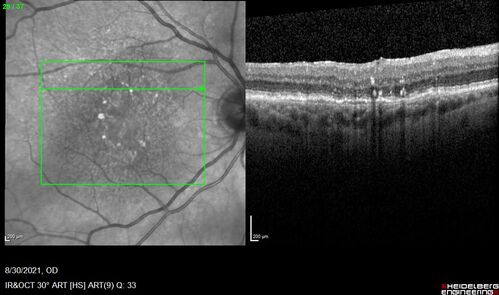

Pigment migration in dry age-related macular degeneration

80 year old female. Dry AMD with GA in the left eye and pigment migration visible on OCT scan.

VA 20/40 OD, 20/160 OS